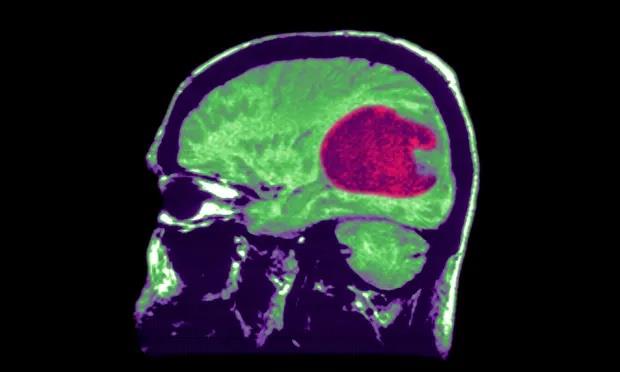

Ảnh chụp X-quang cho thấy khối u thần kinh đệm - khối u não phổ biến nhất ở bệnh nhân ung thư. Ảnh: Getty Images

Trang The Guardian (Anh) đưa tin trong nhiều thập kỷ qua, các nhà nghiên cứu khoa học thần kinh đã phải vật lộn để tìm hiểu về u thần kinh đệm - các khối u nguyên phát bắt nguồn từ nhu mô não, phổ biến nhất ở bệnh nhân ung thư. Loại u thần kinh đệm đặc biệt nguy hiểm này cũng là nguyên nhân gây ra cái chết của con trai Tổng thống Mỹ Joe Biden là Beau Biden và thượng nghị sĩ bang Arizona John McCain.